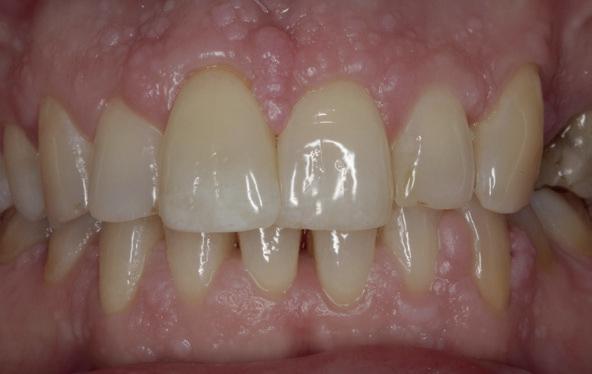

patiënt kon 2 maanden functioneren met de tijdelijke brug, waarna een kort consult werd gepland om te bespreken of hij tevreden was met de esthetiek en functie. Voor de patiënt hoefde niks veranderd te worden (afbeelding 11-14).

14. Portretfoto met tijdelijke brug

Daarna werden de schroefgaten gevuld met Blue M gel, teflon tape en composiet (afbeelding 19 en 20). Patiënt was zich zeer tevreden met het functionele en esthetische eindresultaat (afbeelding 19 en 20). Er was ook een nette hoektand en frontgeleiding. Voor de fonetiek werd een filmpje opgenomen, de F en de S werden netjes uitgesproken (afbeelding 21). De patiënt vervolgt zijn parodontale nazorg bij de mond-

hygiënist waarbij ook de mondhygiëne bij de brug wordt gecontroleerd. Op de OPT na 2 jaar (afbeelding 22) is het botniveau rondom de implantaten stabiel en is patiënt tevreden met zijn vaste brug.